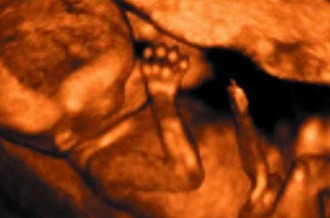

2020-08-03 - De acuerdo al certificado de defunción, las muertes se deben por prematurez, asfixia perinatal e hipoxia